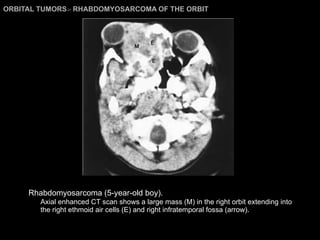

RHABDOMYOSARCOMA M/C primary orbital malignancy in children. M/C soft-tissue malignancy of childhood.  RMS area. Head and neck = 35% GU system = 23% Extremities for = 17%.  10% occur primarily in orbit. 10% metastasize to / invade orbit.

RHABDOMYOSARCOMA Rapidly progressive exophthalmos + proptosis of upper lid. Metastases: lung, bone marrow, cervical lymph nodes (rare).

RHABDOMYOSARCOMA Imagings: Location:  superior orbit / retrobulbar (71%), lid (22%), conjunctiva (7%)  Large soft-tissue mass with ill-defined margins with significant enhancement. Extraocular muscles not involved. Heterogeneous : hemorrhage. Extension into preseptal space, adjacent sinus, nasal cavity, intracranial cavity. Bony erosion may present. MRI : Iso/Hypo on T1WI and  Hyper on T2WI.

ORBITAL TUMORS >  RHABDOMYOSARCOMA OF THE ORBIT Rhabdomyosarcoma (5-year-old boy).   Axial enhanced CT scan shows a large mass (M) in the right orbit extending into the right ethmoid air cells (E) and right infratemporal fossa (arrow).